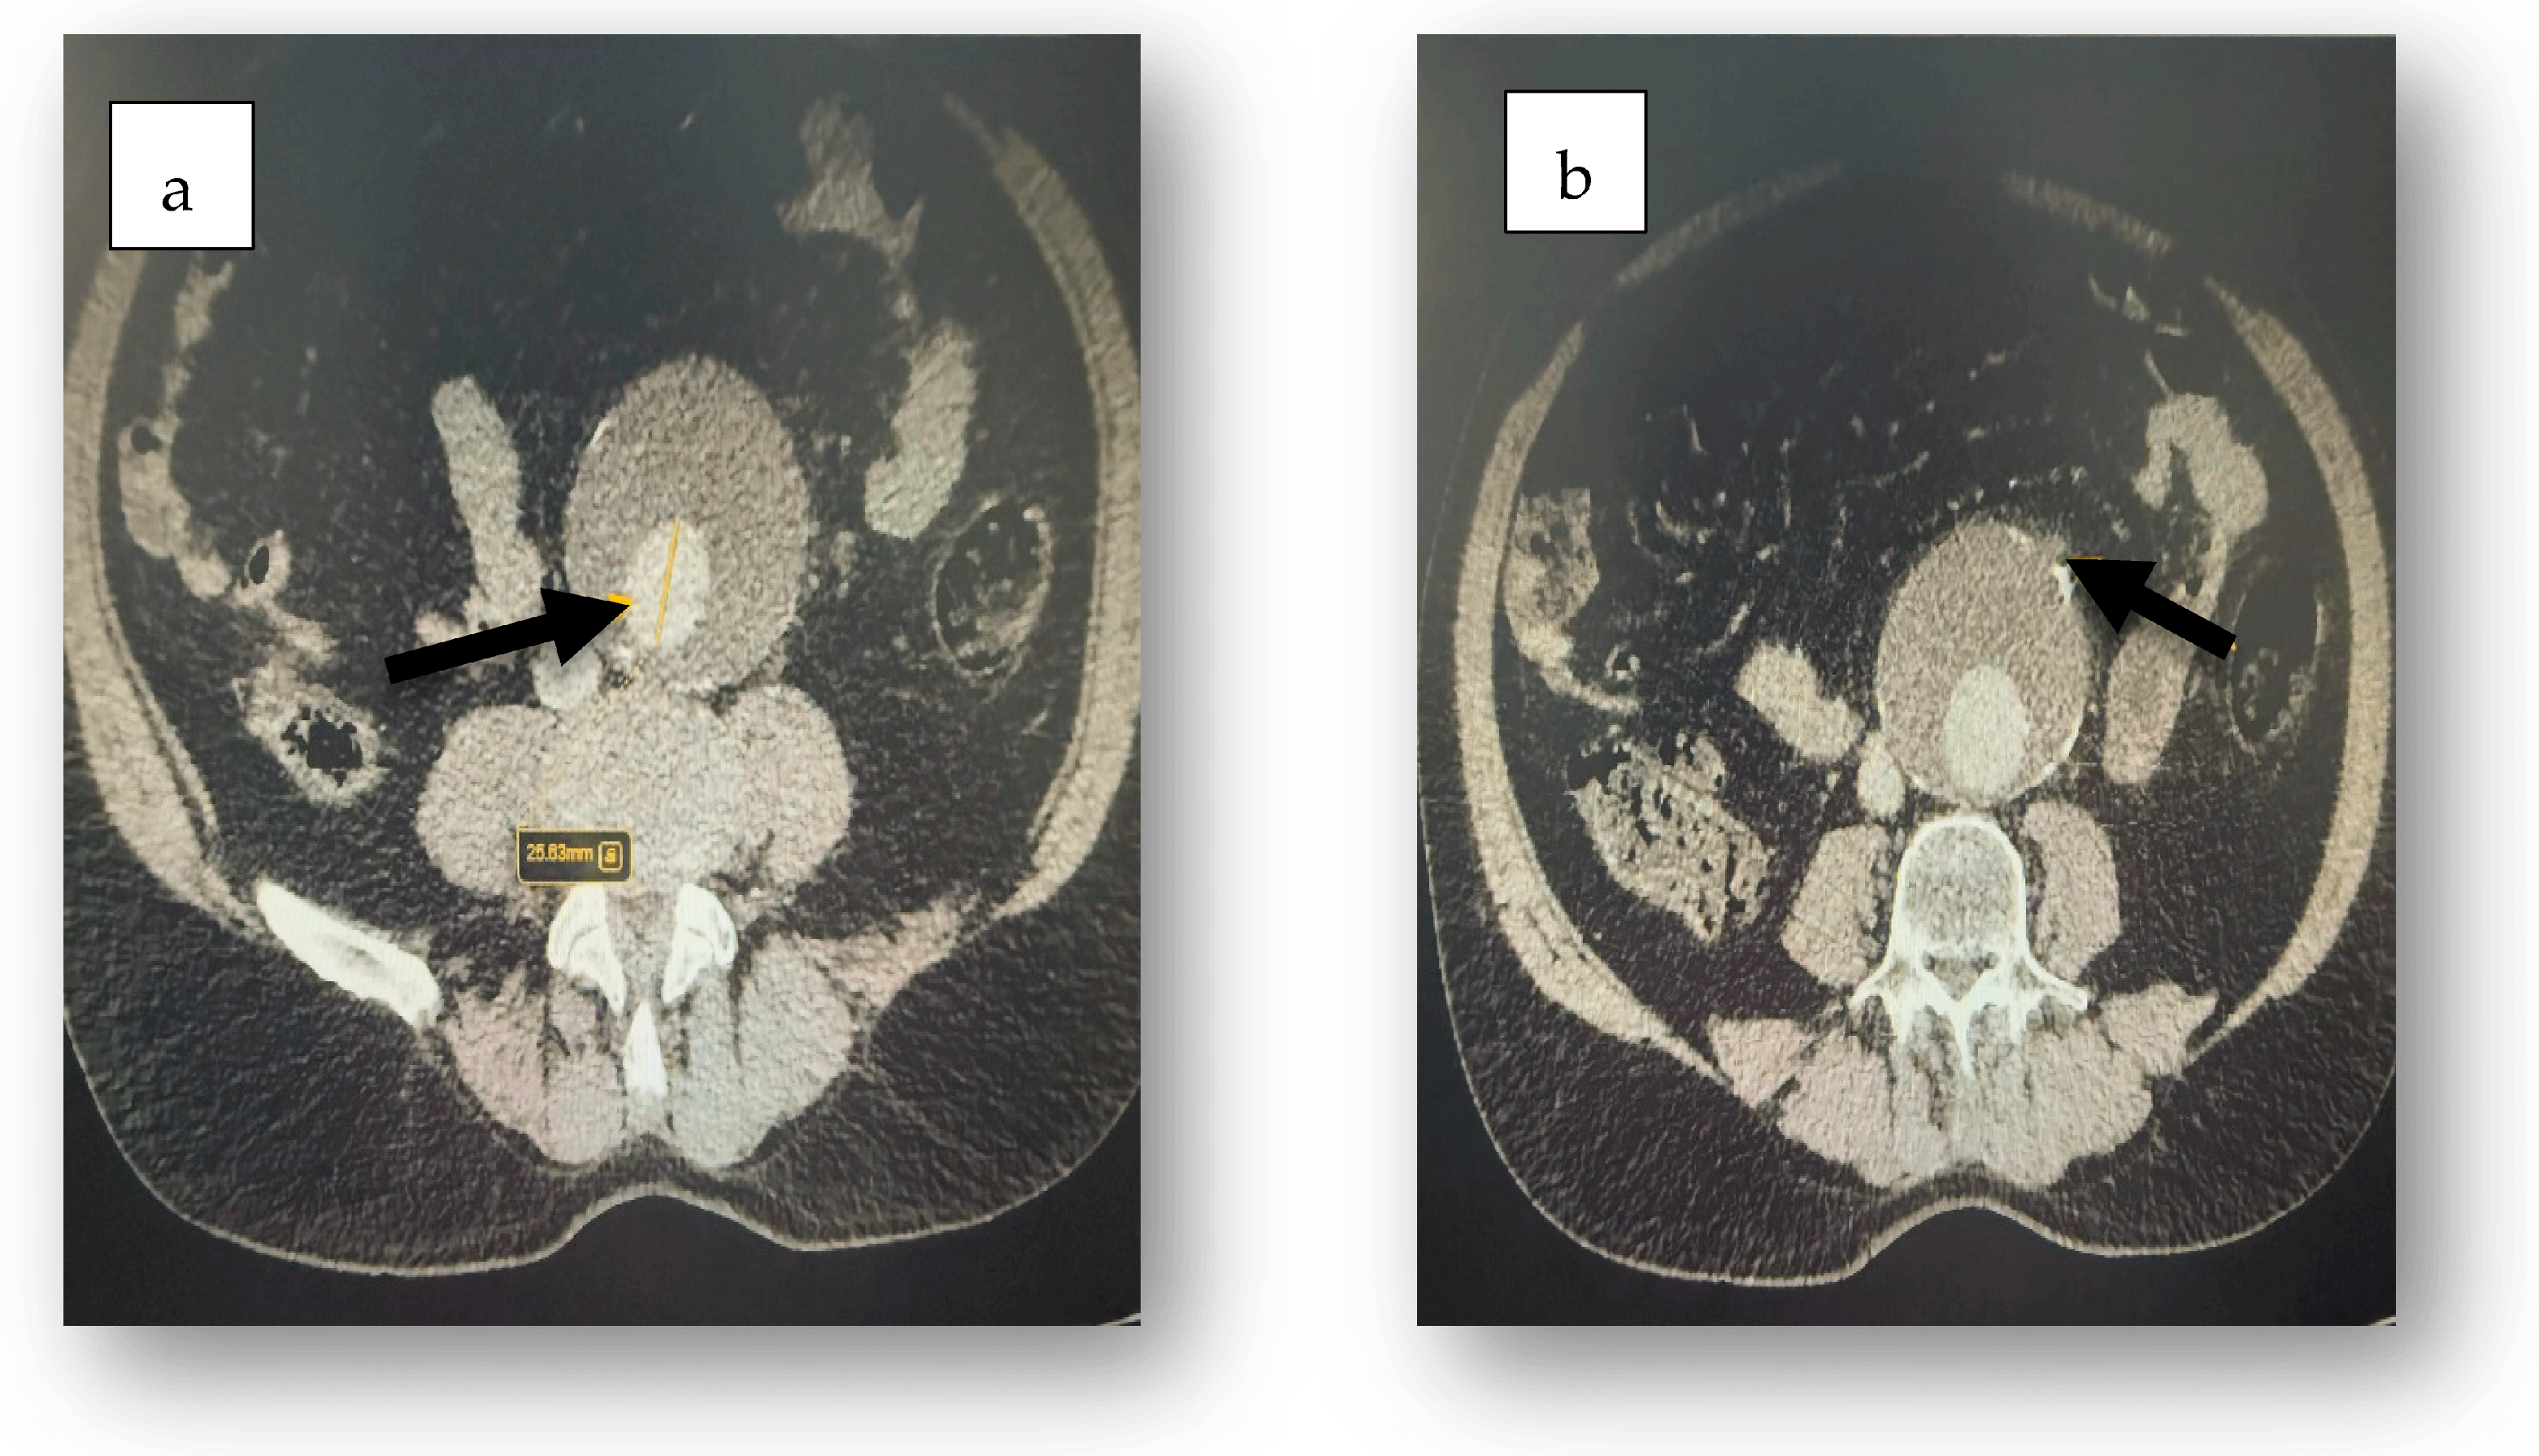

2. Case Report